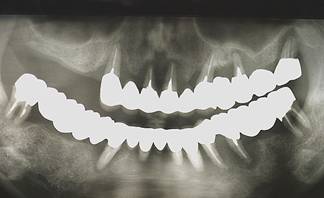

術前パノラマレントゲン写真。根の周りが黒くなり、骨がなくなっていることがわかります